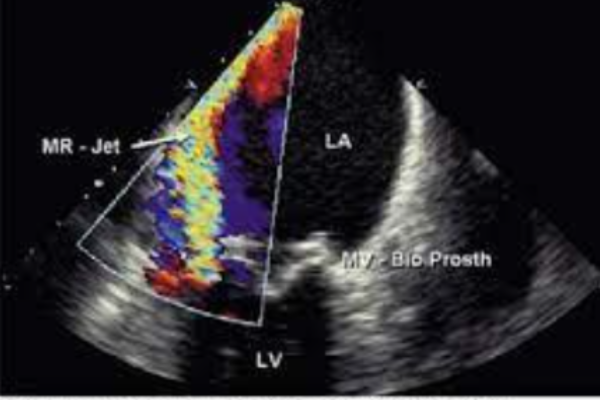

Siêu âm qua thực quản đặc biệt nhạy trong phát hiện hở van hai lá nhân tạo, vì khi đó hình ảnh nhĩ trái được thấy rõ do đó sẽ tránh được nhiễu sinh ra bởi các thành phần kim loại của van nhân tạo.

- Hở cạnh van nhân tạo (sự xuất hiện của dòng chảy bên ngoài vòng van nhân tạo) là không bình thường, mặc dù đôi khi những dòng hở nhỏ cũng có thể thấy ở giai đoạn sớm ngay sau khi phȁu thuật thay van. Hở cạnh van nhân tạo là do vòng van nhân tạo không được khâu chắc vào vị trí vòng van hai lá của bệnh nhân, có thể do lỗi kỹ thuật hoặc do viêm nội tâm mạc nhiễm khuẩn . Hở cạnh van nhân tạo thường cũng hay xảy ra ở bệnh nhân bị vôi hóa vòng van hai lá.

3.2 Hở trong van nhân tạo

Van nhân tạo cơ học có dòng phụt ngược trong thời kỳ đóng của van vị trí bên trong vòng van nhân tạo (hở trong van sinh lý). Những “dòng phụt thì đóng” này là một biểu hiện bình thường và không nên bị nhầm với hở bệnh lý. Nói chung, chúng có thể được phân biệt dễ dàng với dòng hở bệnh lý. Nguyên nhân gây hở trong van bệnh lý bao gồm “pannus” hoặc huyết khối làm cản trở cánh van đóng.